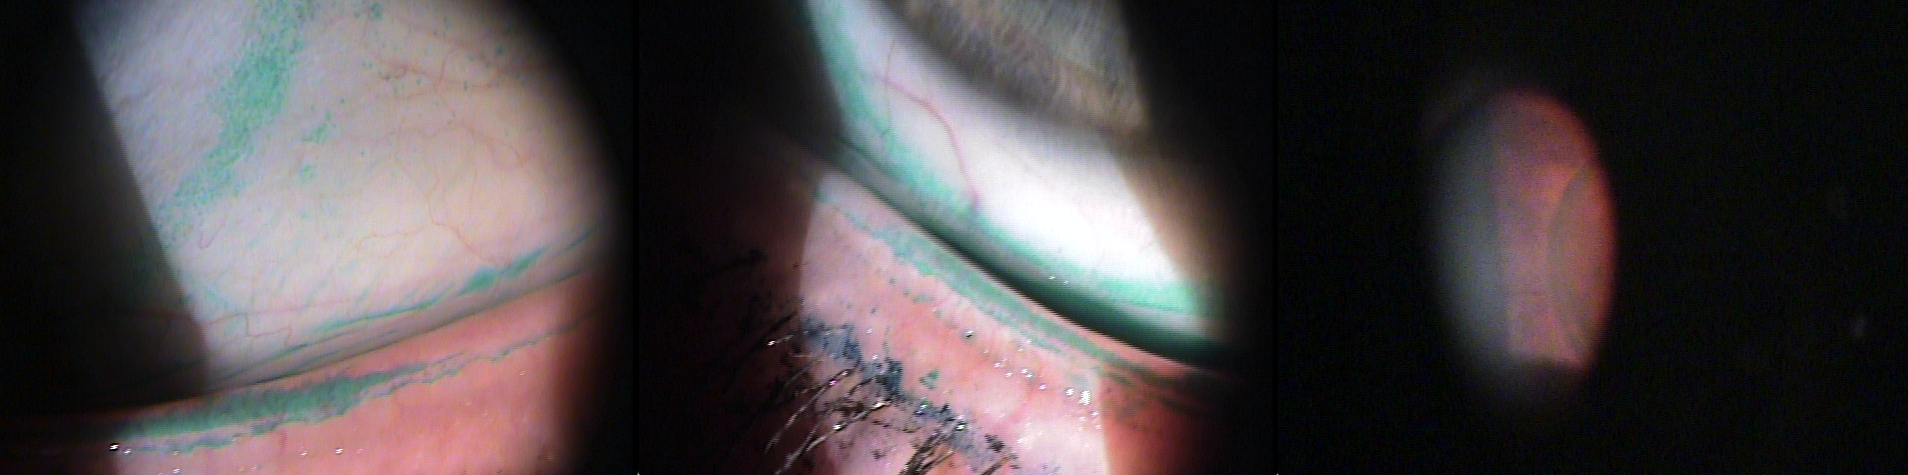

A poor ocular surface is a common condition in glaucoma patients due to the incidence of dry eye, age, and use of benzalkonium chloride (BAK). Poor compliance with glaucoma therapy can result. Use of point-of-care testing can help identify patients with a poor ocular surface and drive treatment decisions. Treatment options, including surgical, are discussed.